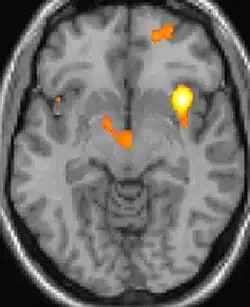

| Positron emission tomography (PET) shows brain areas being activated during pain. | ||

Positron emission tomography (PET) scans indicate the brain areas which are activated during attack only, compared to pain free periods. These pictures show brain areas that are active during pain in yellow/orange color (called "pain matrix"). The area in the center (in all three views) is activated only during cluster headaches. The bottom row voxel-based morphometry shows structural brain differences between individuals with and without CH; only a portion of the hypothalamus is different.[36]